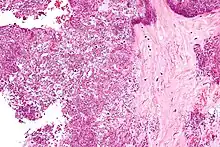

Arthrocentesis, or removing synovial fluid from the affected joint, is performed to test the synovial fluid for the calcium pyrophosphate crystals that are present in CPPD. When stained with H&E stain, calcium pyrophosphate crystals appears deeply blue ("basophilic").[10][11] However, CPP crystals are much better known for their rhomboid shape and weak positive birefringence on polarized light microscopy, and this method remains the most reliable method of identifying the crystals under the microscope.[12] However, even this method has poor sensitivity, specificity, and inter-operator agreement.[12]